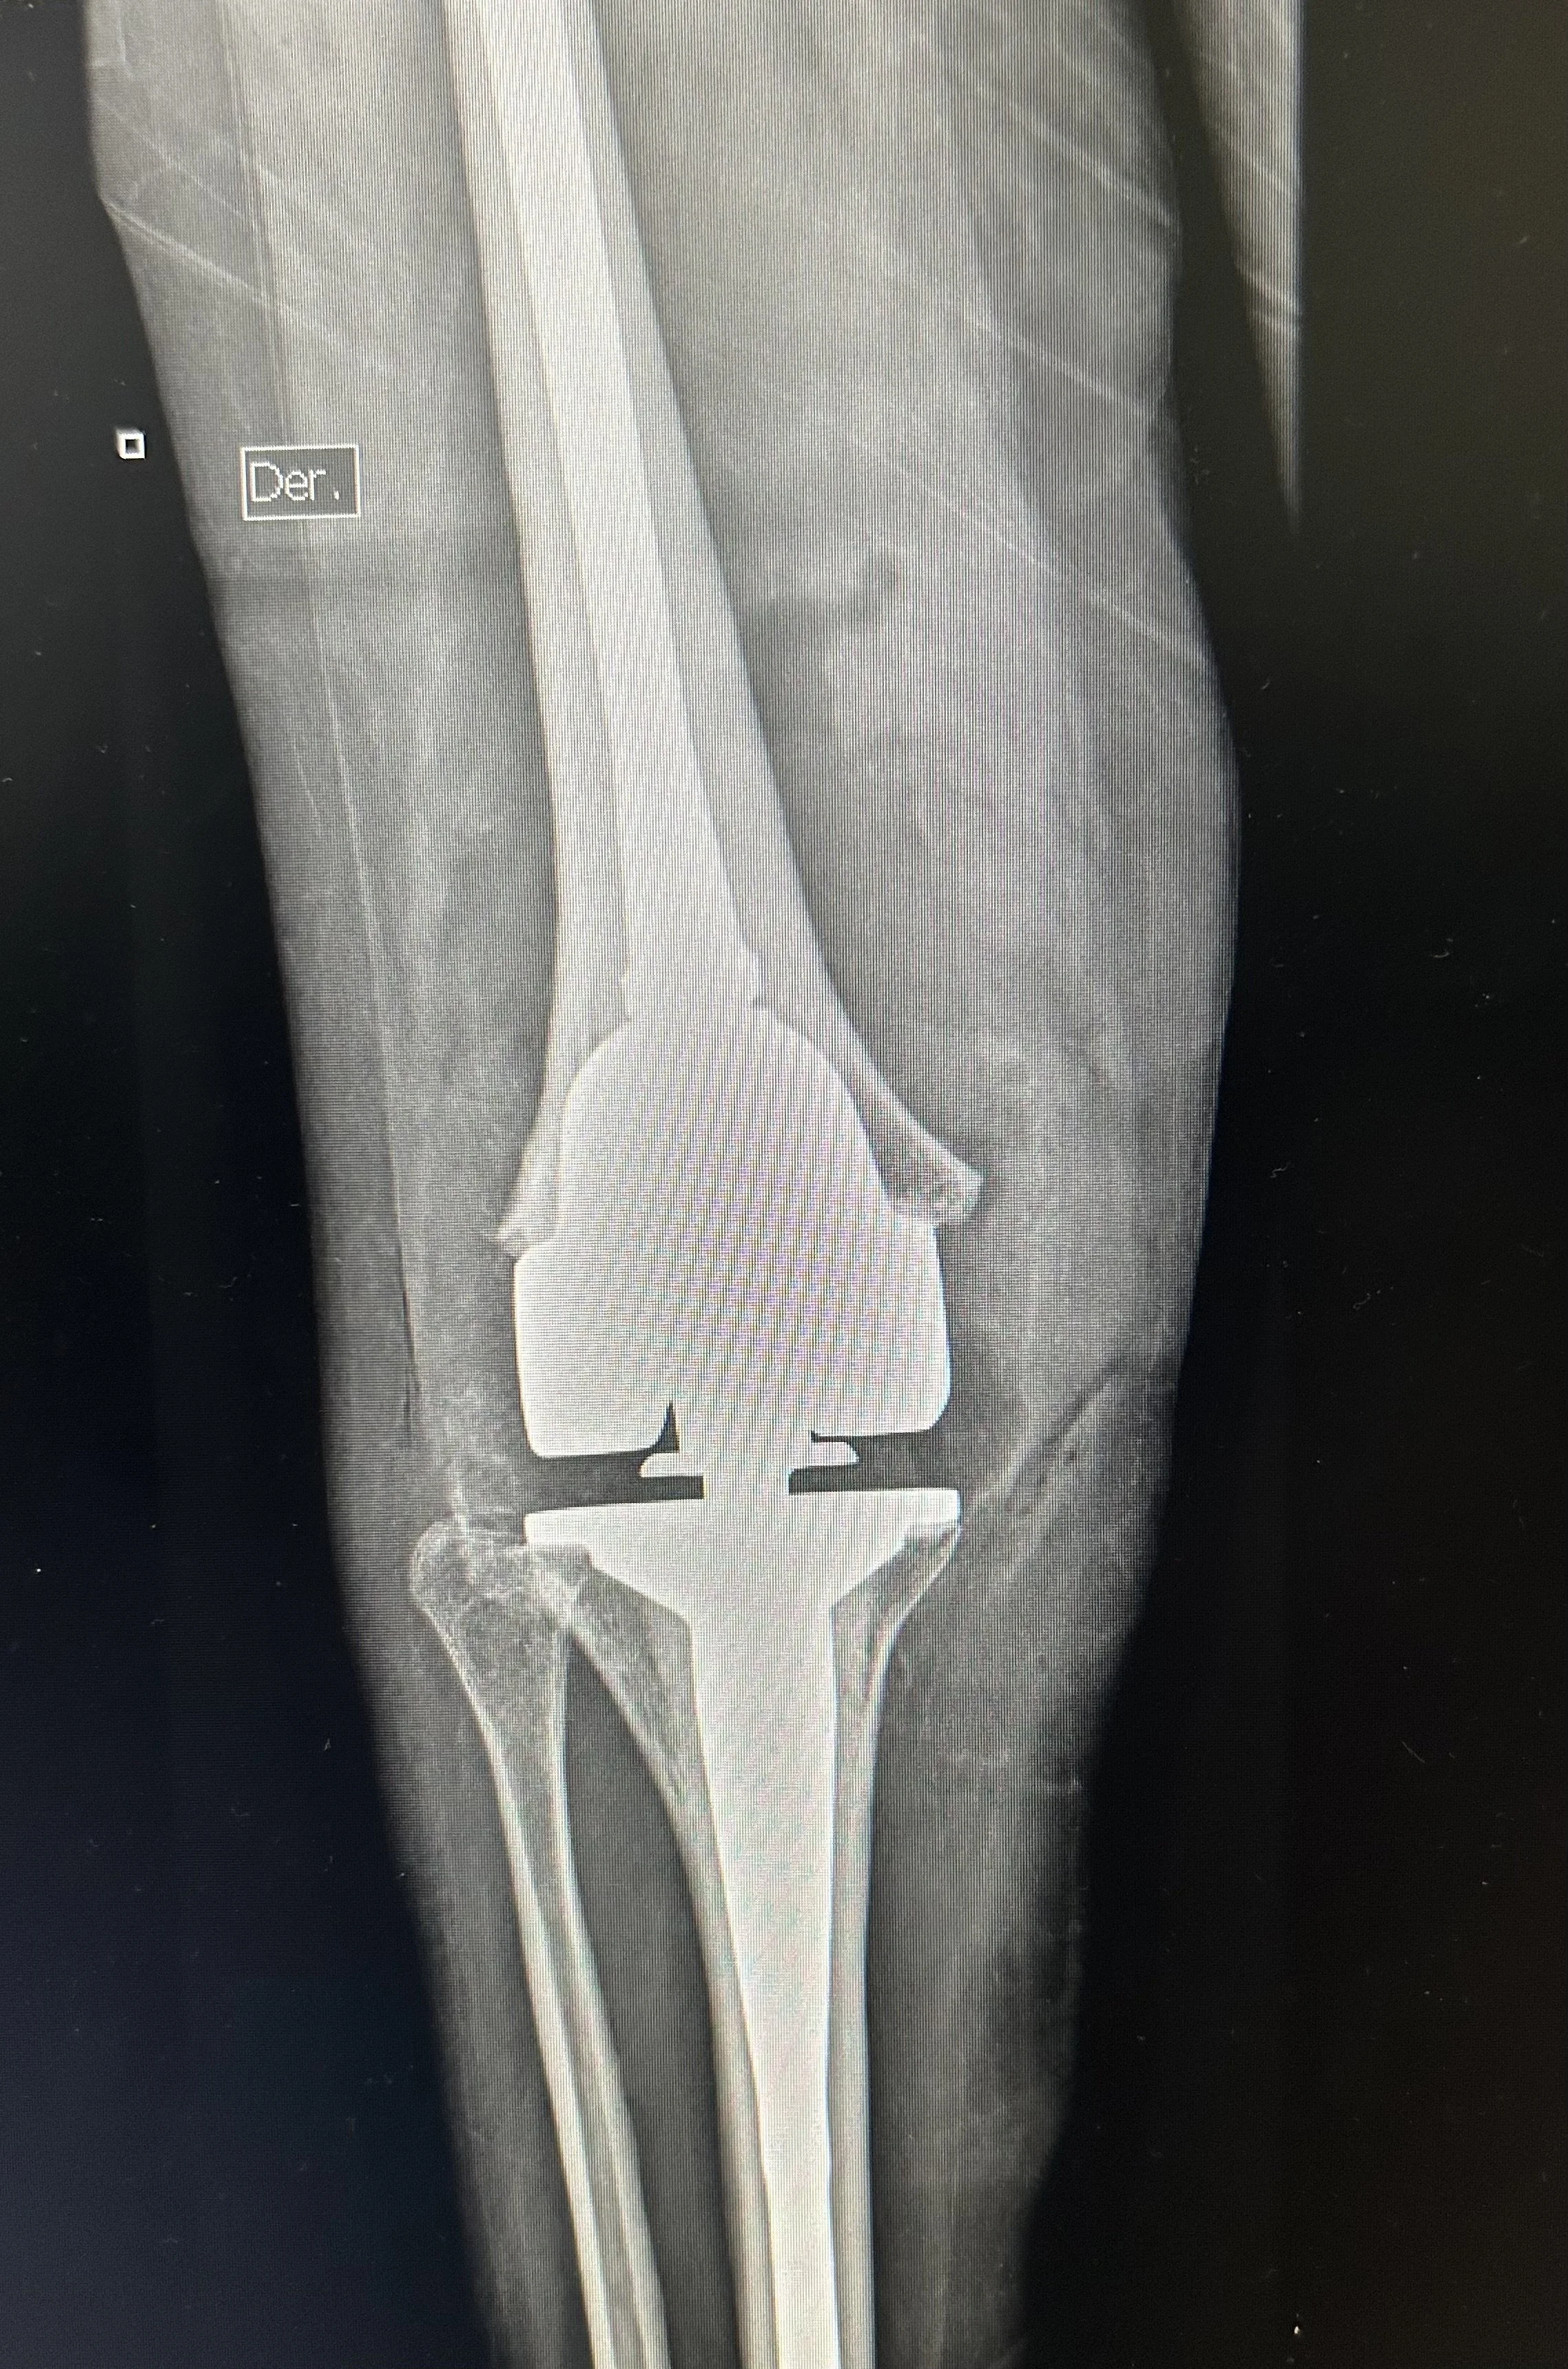

Sandra, a 29 y.o. The woman had been gathering firewood and reportedly fell 40 feet from a tree.  Because firewood is the primary source of energy for cooking in the rural areas of Guatemala, this practice often involves the women and children in the family. She had a significant injury to her knee, leaving it painful and not functional.  The Hope in Motion surgical teams were able to implant a state-of-the-art hinged knee replacement prosthesis to provide both stability and an improvement in her pain and function.